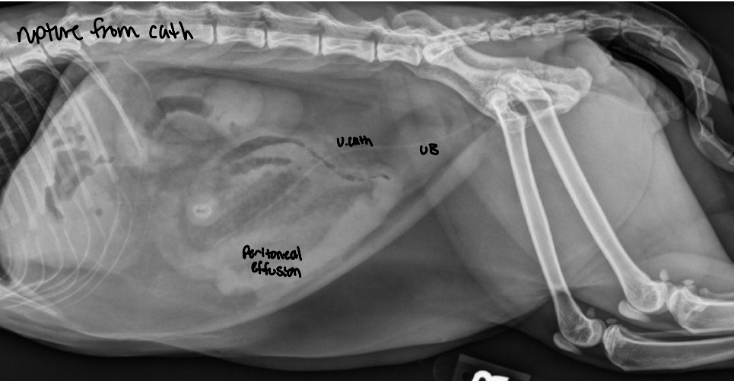

preferred method to ID ureteral rupture

EU/IVP

dog with trauma hx has decreased RP detail and leakage of contrast material into both the peritoneal and RP space

ruptured ureter

avulsion — peritoneal space

rupture — RP space